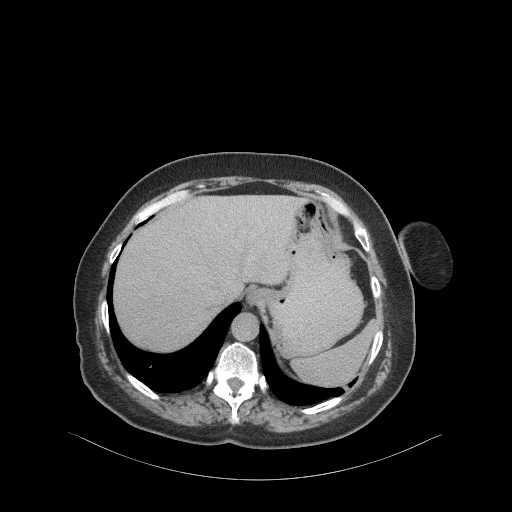

Original NATIVE CT scan (input)

Full window (WL 1023.5, WW 4095 β†’ Low βˆ’1024, High +3071)